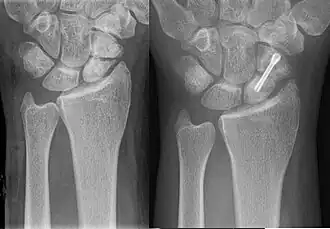

An X-ray showing a fracture through the waist of the scaphoid | |

A more obvious scaphoid fracture on a scaphoid view X ray

For non and minimally displaced fractures (up to 2mm) of the scaphoid waist, cast immobilisation (with surgical fixation for non-united fractures at 6 to 12 weeks) is as effective as immediate surgery fixation and results in less complications.[14][15][16] The choice of short arm, short arm thumb spica or long arm cast is debated in the medical literature and no clear consensus or proof of the benefit of one type of casting or another has been shown; although it is generally accepted to use a short arm or short arm thumb spica for non displaced fractures.[7]

Percutaneous screw fixation is recommended over an open surgical approach when it is possible to achieve acceptable bone alignment closed as minimal incisions can preserves the palmar ligament complex and local vasculature, and help avoid soft tissue complications. This surgery includes screwing the scaphoid bone back together at the most perpendicular angle possible to promote quicker and stronger healing of the bone. Internal fixation can be done dorsally with a percutaneous incision and arthroscopic assistance [17] or via a minimal open dorsal approach,[18] or via a volar approach in which case slight excavation of the edge of the trapezium bone may be necessary to reach the scaphoid as 80% of this bone is covered with articular cartilage, which makes it difficult to gain access to the scaphoid.[19]